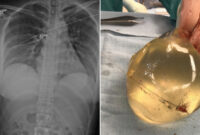

Woman's Breast Implant Deflects Bullet, Saving Her Life – CNN

Woman's breast implant deflects bullet, saving her life - CNN

www.cnn.com

woman breast implant bullet implants her chest gunshot cnn after shot silicone old when wound deflects saving life womans top